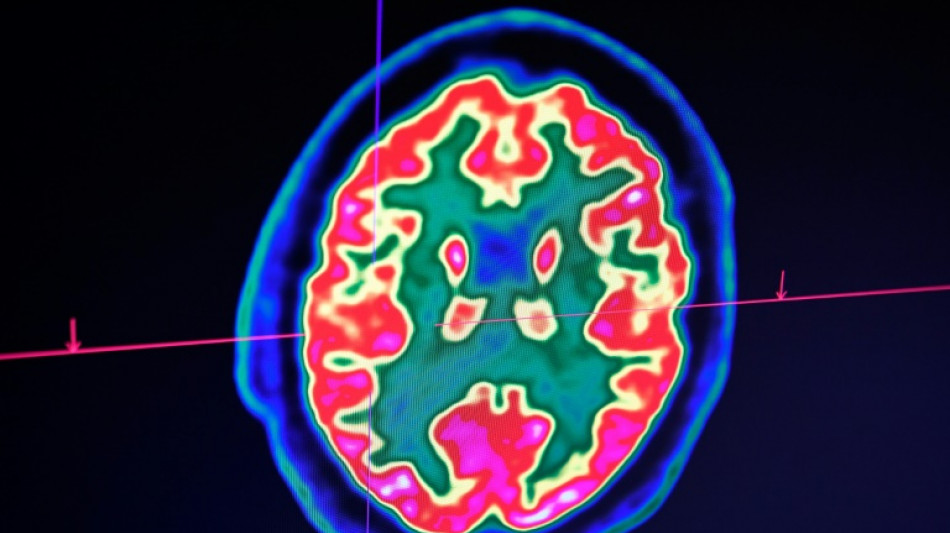

Cancer du cerveau: la guérison d'un enfant ouvre de grands espoirs pour la recherche / Photo: © AFP